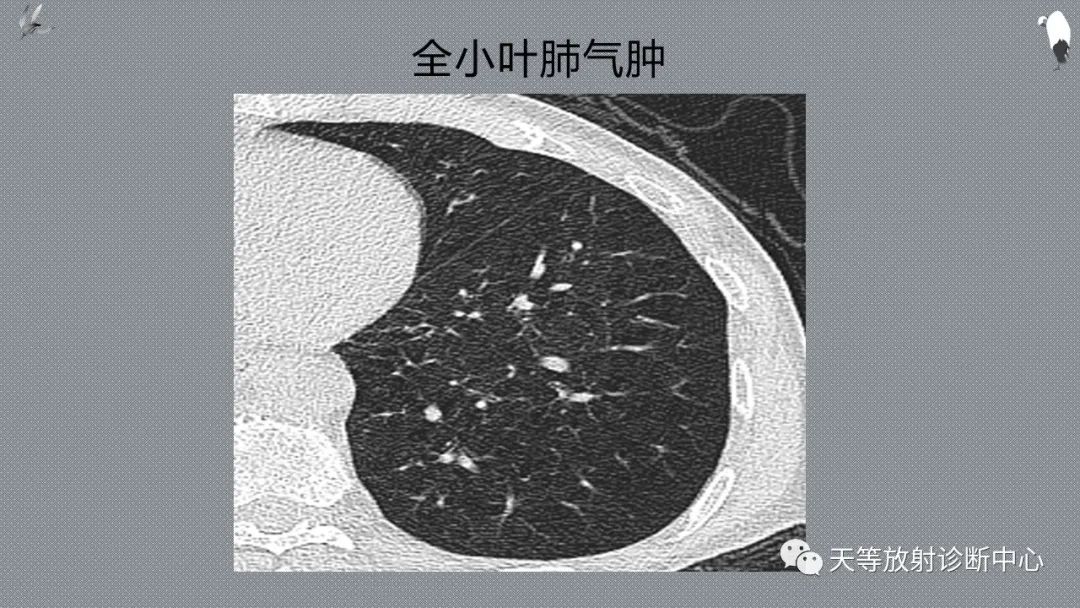

应该注意以下鉴别:全小叶肺气肿、肺动脉高压、哮喘的鉴别